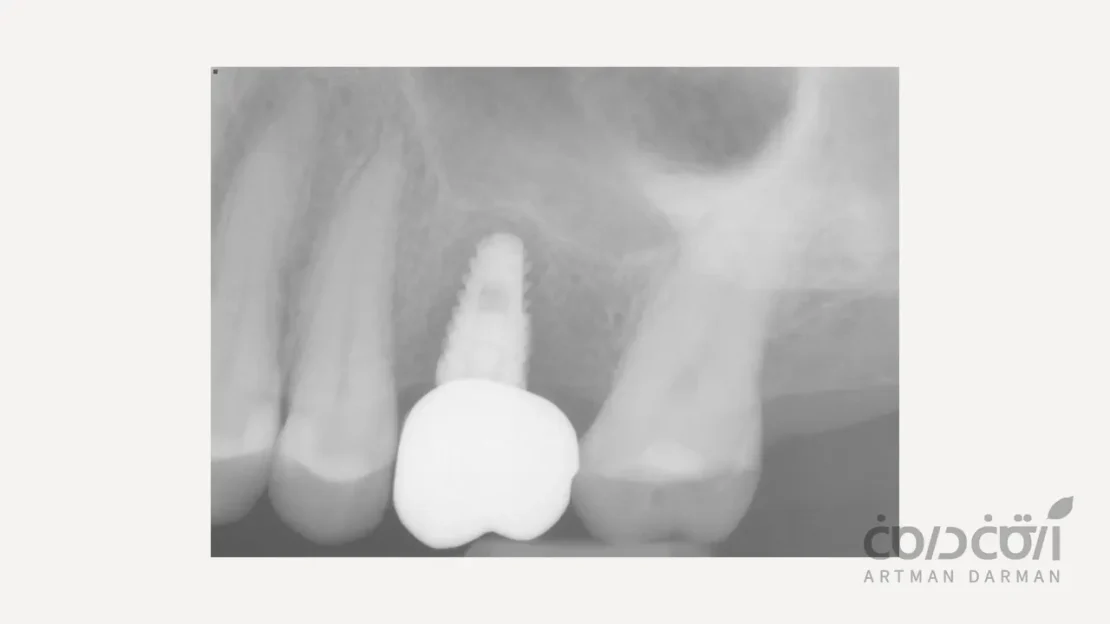

10 آذر مقالات, مقالات ایمپلنت دندان آیا پیوند استخوان در ایمپلنت دندان ضروری است؟ (پاسخ کامل به این سوال) 19 آذر 1404 توسط آرتمان درمان 0 دیدگاه در برخی موارد نیاز است تا پیش از انجام جراحی ایمپلنت دندان، پیوند استخوان صورت بگیرد. در این نوشتار هرچیزی که میبایست در خصوص پیوند است... ادامه مطلب